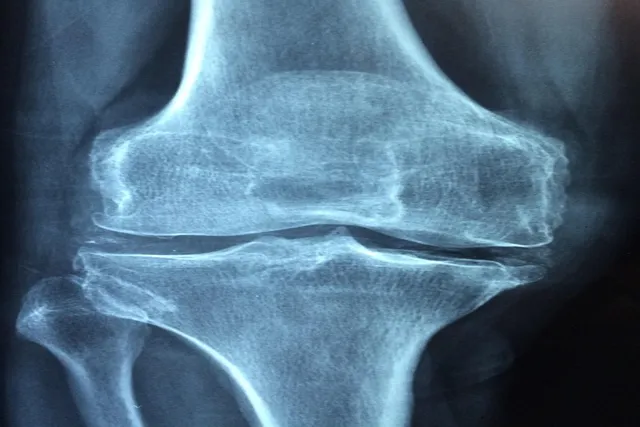

골다공증은 뼈의 질량이 줄어들고, 뼈의 구조가 약해지는 질환입니다. 흥미롭게도, 이는 주로 폐경 후 여성에게서 많이 발생하지만, 남성에게도 발생할 수 있습니다. 우리 몸은 지속적으로 뼈를 생성하고 파괴하는 과정을 거칩니다. 그러나 골다공증 환자의 경우, 뼈 손실이 뼈 생성보다 더 빠르게 진행되므로 뼈가 약해지는 것입니다. 골다공증의 증상은 의외로 미미하고, 많은 경우에는 골절이 발생하기 전까지 자각하지 못하는 경우가 많습니다.

골다공증을 발생시키는 원인은 여러 가지가 있습니다. 주요 원인 중 하나는 호르몬 변화입니다. 예를 들어, 여성은 폐경기를 맞이하면서 에스트로겐 수치가 감소하고 이는 뼈의 밀도를 낮추는 결과를 초래합니다. 또 다른 원인은 유전적 요인인데, 가족력이 있는 경우 골다공증에 걸릴 확률이 높아집니다. 마지막으로 영양결핍도 무시할 수 없는 요인입니다. 칼슘이나 비타민 D의 부족은 뼈 건강에 영향을 미치므로 꼭 주의해야 합니다.